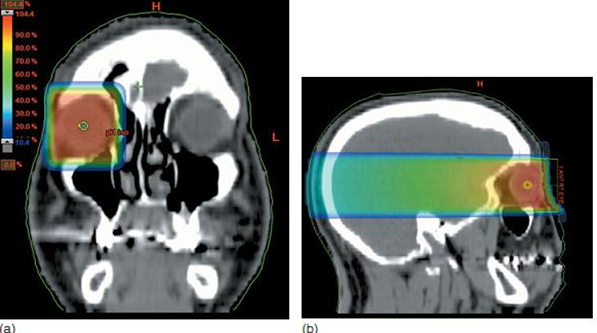

Các chùm tia khi xạ trị giảm nhẹ cho di căn màng mạch có thể xác định được trong mô phỏng. Trường chiếu 4x4 cm đánh dấu trên bề mặt với biên độ trước ở ngoài khóe mắt và tâm trường chiếu ở đồng tử. Trường chiếu chếch về phía sau 5° để tránh hoàn toàn thấu kính ở mắt đối bên. Xem xét phân bố liều lượng theo Dmax hoặc độ sâu của tổn thương di căn trên chẩn đoán hình ảnh.

Xạ trị giảm nhẹ cho di căn tại màng mạch.

a. Vị trí tổn thương (đầu mũi tên)

b. Phân bố liều lượng trên trường chiếu chếch 5o về phía sau

Một cách khác là sử dụng một chùm tia thẳng trước 4 x 4 cm tập trung vào đồng tử và tia khi mắt mở để giảm thiểu liều vào thấu kính. Để điều trị di căn màng mạch hai bên, sử dụng chùm tia đối xứng, và một trường chếch 5° về phía sau.